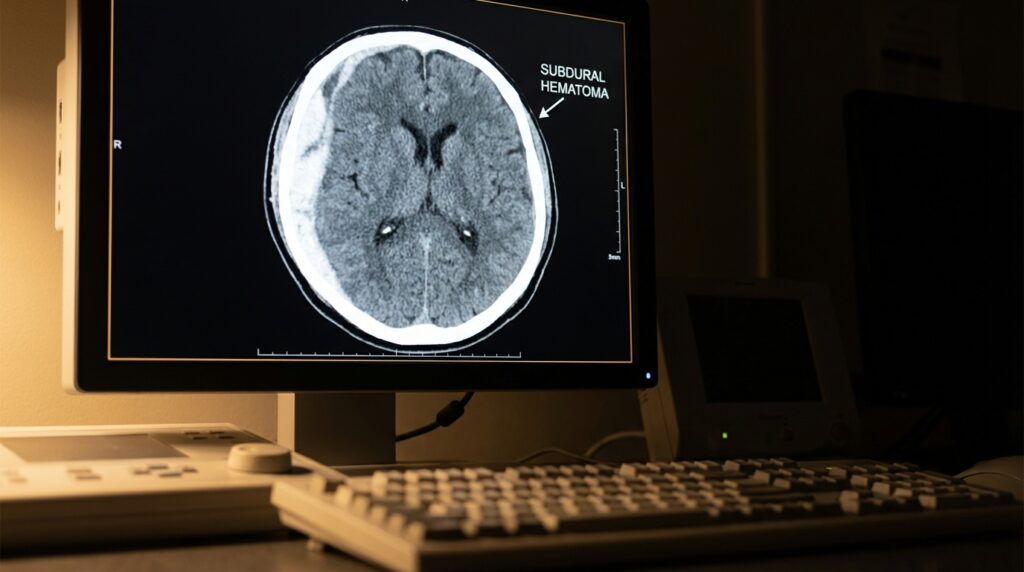

Traumatic brain injury is the “invisible” catastrophic injury. A broken leg shows up on an X-ray. A TBI often does not — at least not on the scans an ER runs in the first hour after an accident. The Centers for Disease Control and Prevention estimate that more than 2.8 million Americans sustain a traumatic brain injury each year, and California’s share of that count is the largest of any state. Mild TBIs (including concussions) are routinely missed on initial imaging. Moderate and severe TBIs produce lifetime consequences — cognitive impairment, personality change, memory loss, executive-function deficits, mood disorders, sleep disruption, post-traumatic seizures, and in the worst cases coma and wrongful death.

The hardest part of a TBI case is translating modern neuroscience into evidence a jury will accept. Traditional CT scans catch bleeding and major structural damage. They miss most mild TBI. Diffusion Tensor Imaging (DTI), advanced functional MRI, and quantitative EEG can detect the microscopic axonal injury that causes lasting cognitive dysfunction after “mild” TBI. Neuropsychological testing — a multi-hour battery administered by a PhD neuropsychologist — documents the specific cognitive deficits the client is experiencing. Life-care planners translate the functional impairment into projected lifetime costs: cognitive rehabilitation, speech therapy, occupational therapy, supervision, case management, home modification, assistive technology, and future medical care. Vocational experts document the loss of earning capacity. Economists reduce the future stream of losses to present value.

How is a brain injury diagnosed after an accident?

Initial evaluation in the ER includes CT scan and the Glasgow Coma Scale. Follow-up MRI catches many findings missed by CT. Advanced imaging like DTI and functional MRI can detect microscopic axonal injury. Neuropsychological testing administered by a PhD documents specific cognitive deficits.